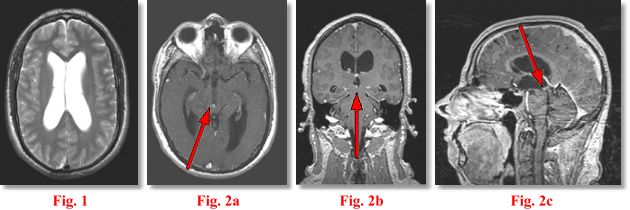

CLINICAL PRESENTATION: This patient in his early forties presented to the office of Dr. A. Farrukh and Dr. M.K. Dhillon* with progressive intermittent headaches and some balance and bladder dysfunction. An outside scan (not shown) suggested possible obstruction at the level of the aqueduct of Sylvius. The patient was referred to AIC for high-resolution MRI of the brain with 1 mm sections through the aqueduct and CSF flow study.

IMAGING FINDINGS: The study was performed on AIC’s high-field Siemens Symphony scanner. Fig. 1 shows an axial T2 weighted image of the ventricles demonstrating moderate hydrocephalus. Fig. 2a-c are post-contrast axial (5 mm), coronal (1 mm) and sagittal (1 mm) T1 weighted images through the aqueduct. They demonstrate a subtle tiny 4 mm enhancing mass (arrows) at the entry zone into the aqueduct at the junction with the inferior 3rd ventricle.

DIFFERENTIAL DIAGNOSIS: This is a solid mass in the ventricular system. The following DDX was rendered at the time of the scan: meningioma, ependymoma, subependymoma, PNET, a vascular lesion or, less likely, a glioma or metastasis.

SURGICAL PROCEDURE: The patient underwent surgery at UCLA Medical Center by Neurosurgeon Dr. Marvin Bergsneider including endoscopic ventriculocisternostomy and endoscopic-assisted tumor biopsy and excision. A recent follow-up MRI done at AIC (not shown) showed complete removal of the tumor and resolution of hydrocephalus.

PATHOLOGIC DIAGNOSIS: Pathology revealed a PINEOCYTOMA, obviously in an ectopic location as the tumor was away from the pineal gland, which is posterior to the 3rd ventricle. Final Diagnosis: Ectopic Pineocytoma.